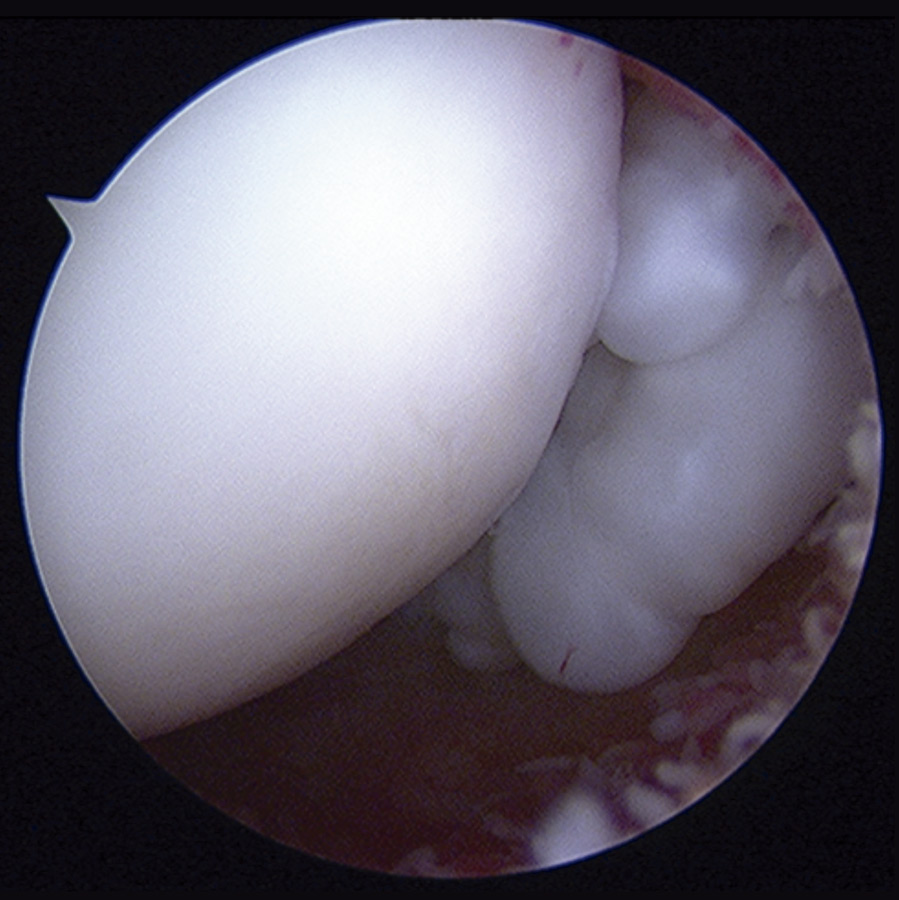

Con el diagnóstico de condromatosis sinovial de hombro derecho se procedió a la realización de una artroscopia, viendo múltiples cuerpos libres intraarticulares, la mayoría de ellos de consistencia cartilaginosa (Figuras 3 y 4) y se procedió a su extracción por vía artroscópica (Figura 5). Tras la cirugía, se remitió a la paciente a recuperación funcional, presentando una buena evolución clínica. La paciente se encuentra asintomática en el momento actual, presentando un balance articular completo.

Figura 3. Imagen artroscópica: cuerpos libres en condromatosis sinovial.

Figura 4. Imagen artroscópica: cuerpos libres en condromatosis sinovial.